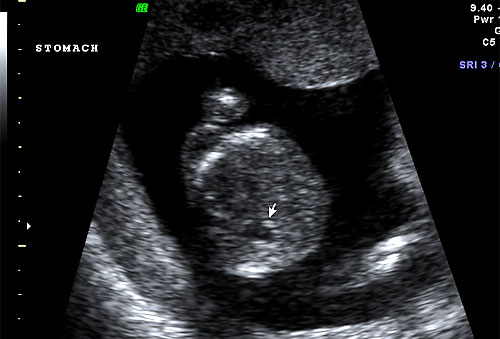

Normal 16 week stomach |